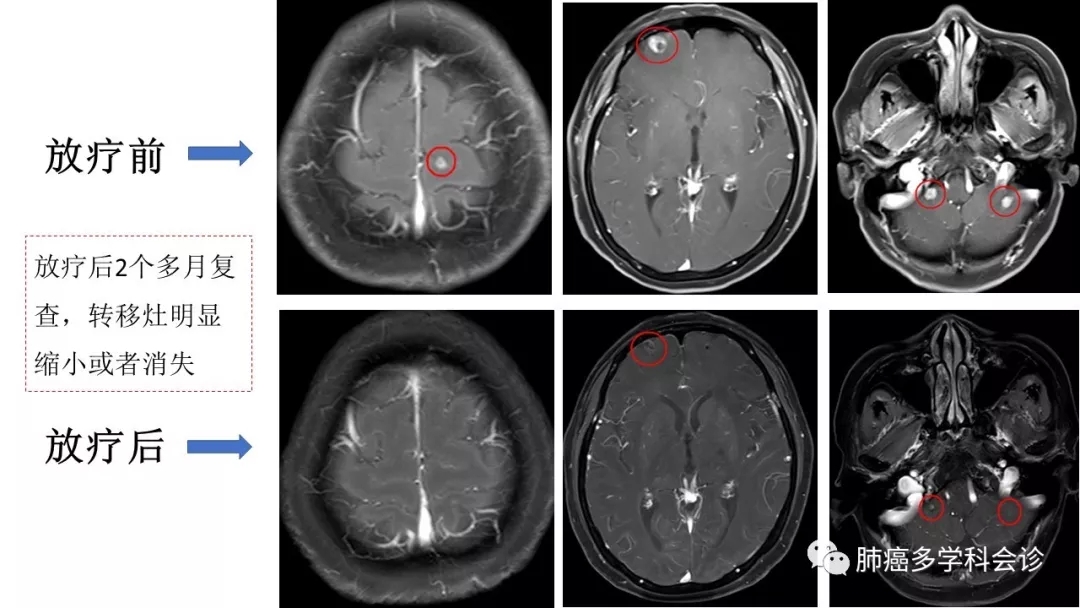

• SRS:(Stereotactic RadioSurgery)立体定向放射外科,应用高度精准的放疗技术,使放射线聚焦在肿瘤部位,病灶受到高剂量照射的同时,最大程度地减少周围正常组织的损伤。一次性完成治疗剂量,像外科手术样去除肿瘤,所以称为放疗“刀”, SF-SRS (single-fraction SRS)